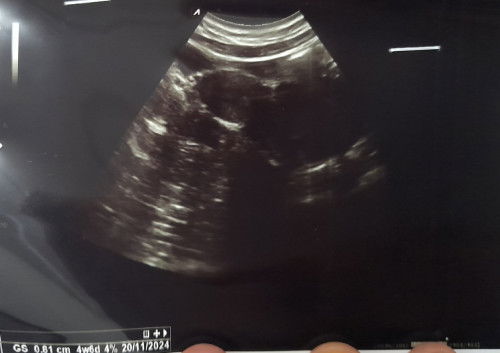

Bun mau nanya dong, ini kantongnya yang mana ya? Atau belum kelihatan? Di keterangan usg nya sih uk 4w6d Maklum bun kehamilan pertama

Posisi kantong dmna

mungkin baru penebalan bun